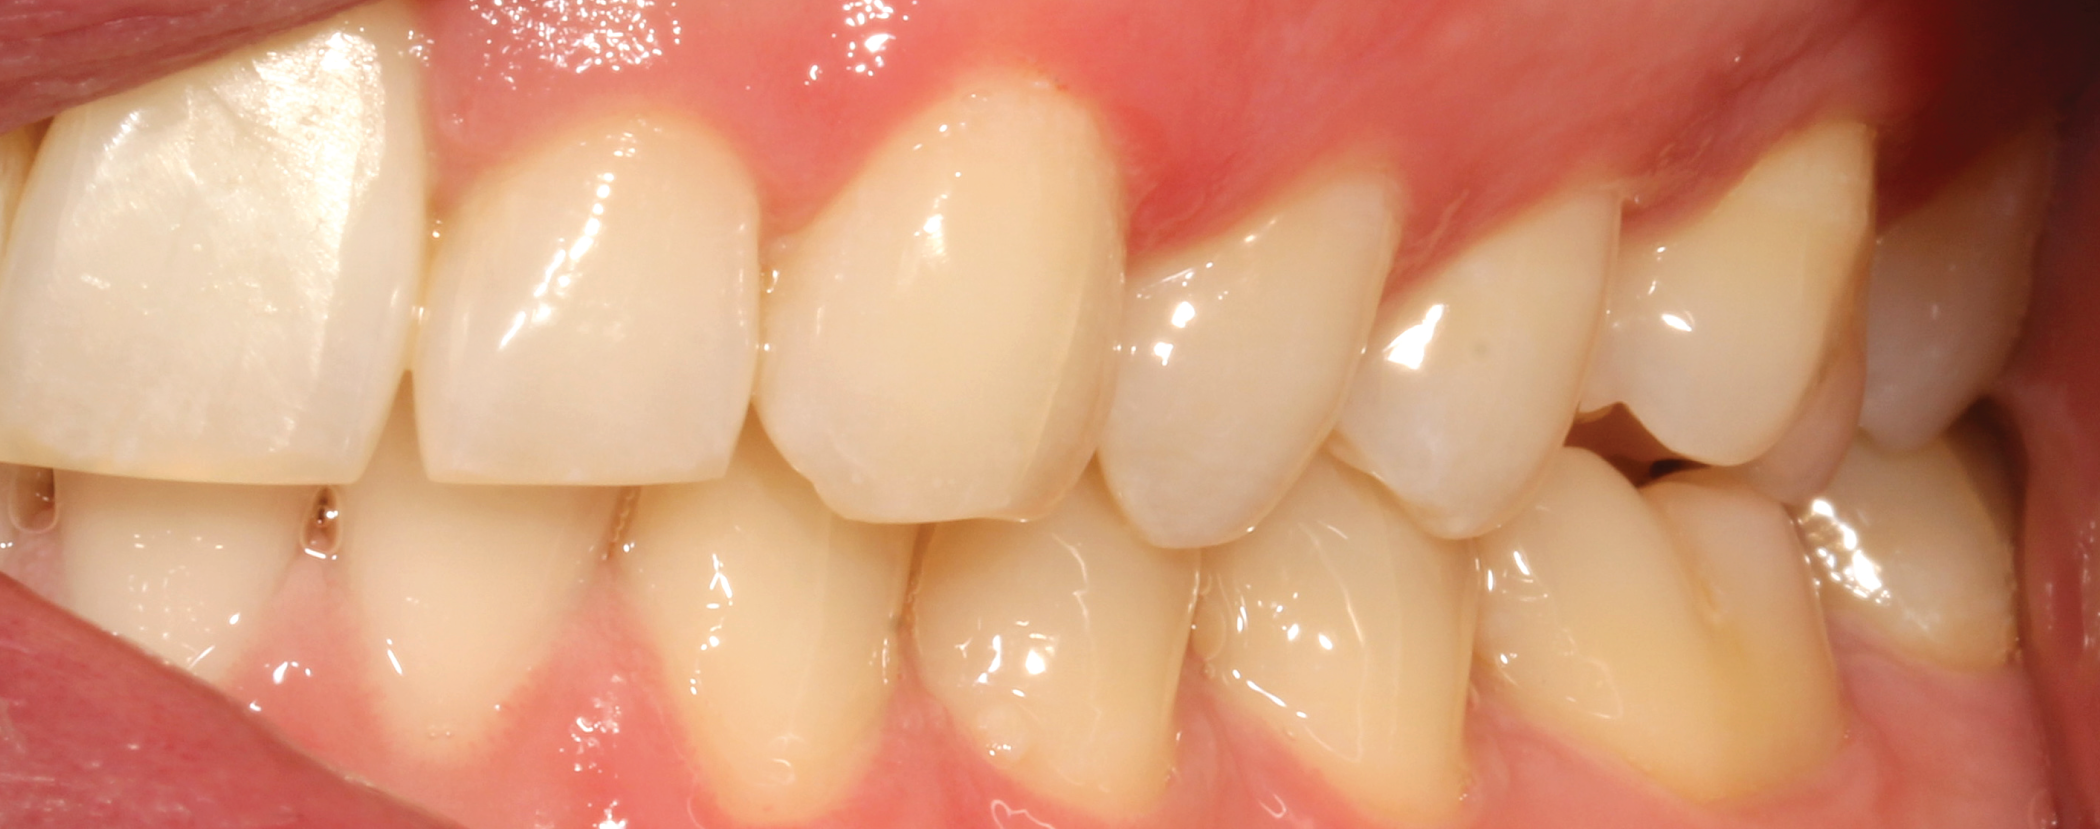

Fig. 7: Pre-op (right lateral view) Fig. 8: Pre-op (left lateral view)